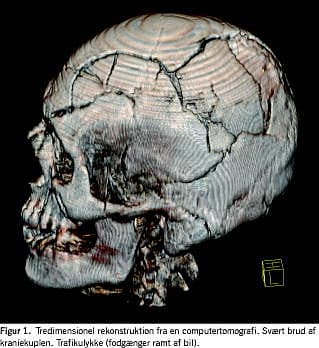

CT er en hurtig undersøgelsesmetode, som er ved at vinde indpas på de retsmedicinske institutter [2-4]. En rutineskanning tager ca. 10 minutter. Informationerne, som er i digital form, kan let lagres, sendes og kopieres. Herved sikres en bedre dokumentation og en bedre mulighed for revurdering af diagnoserne, for eksempel i Retslægerådet, hvilket må betragtes som en gevinst for retssikkerheden. CT-fotografier med f.eks. skudvinkler eller kraniefrakturer vil ofte være mere acceptable til fremvisning for nævninge i en retssag end traditionelle obduktionsfotografier. CT giver indblik i kroppens strukturer in situ, før de forstyrres ved obduktionen [5]. Det kan være en fordel ved kominutte kraniebrud, hvor brudstykkerne falder fra hinanden, når kraniet åbnes (Figur 1), eller til vurdering af graden af forskydning af midtlinjestrukturer (mediastinum og hjerneventrikler). CT giver desuden indblik i områder, som ikke undersøges rutinemæssigt, eller som er vanskeligt tilgængelige, og er velegnet til påvisning af fremmedlegemer (body packers med narkotikaposer i mave-tarm-kanalen) eller luft (luftemboli og pneumothorax) [6, 7]. Postmortel udvikling af forrådnelsesgas kan dog umuliggøre påvisningen af luftemboli. CT kan være til hjælp, når dødfundne skal identificeres, både i enkeltsager og ved massekatastrofer (flystyrt og togkatastrofer) [8-12]. Med CT kan man hurtigt afsløre hofteproteser, kunstige hjerteklapper, gamle knoglebrud eller andet af værdi for identifikationen.